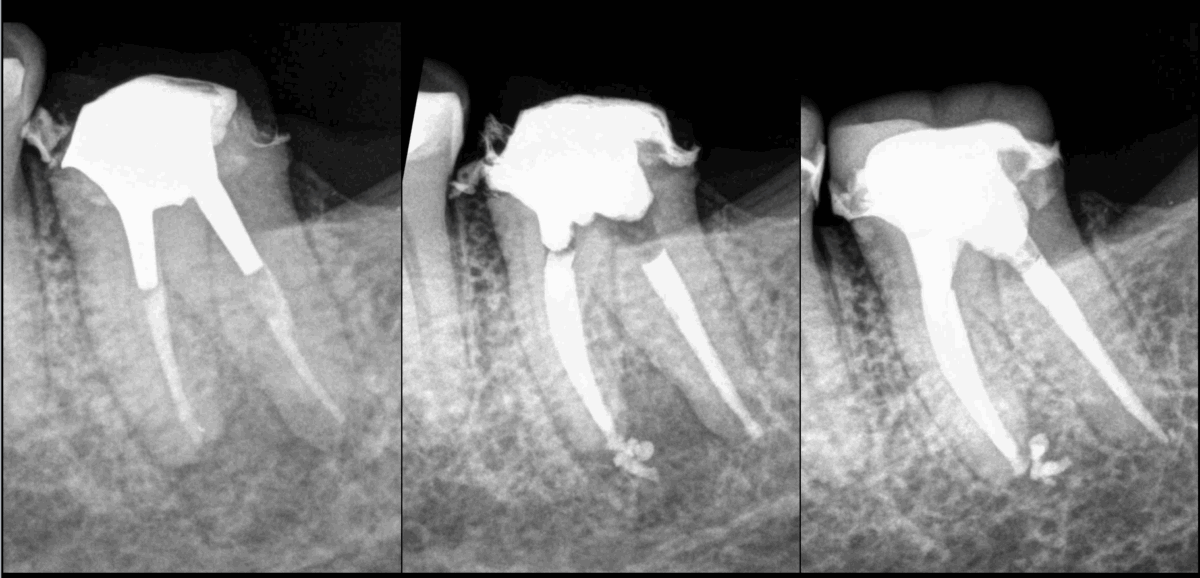

📆 𝐀̀ 𝟏 𝐚𝐧, 𝐥𝐞 𝐫𝐞𝐭𝐫𝐚𝐢𝐭𝐞𝐦𝐞𝐧𝐭 𝐜𝐚𝐧𝐚𝐥𝐚𝐢𝐫𝐞 𝐞𝐬𝐭 𝐞𝐟𝐟𝐢𝐜𝐚𝐜𝐞.

❓ 𝐏𝐨𝐮𝐫𝐪𝐮𝐨𝐢 𝟏 𝐚𝐧 ?

👉 𝐏𝐚𝐫𝐜𝐞 𝐪𝐮𝐞 𝐥𝐞𝐬 𝐞́𝐭𝐮𝐝𝐞𝐬 𝐦𝐨𝐧𝐭𝐫𝐞𝐧𝐭 𝐪𝐮𝐞 𝐥𝐚 𝐩𝐥𝐮𝐩𝐚𝐫𝐭 𝐝𝐞𝐬 𝐞́𝐜𝐡𝐞𝐜𝐬 𝐬𝐮𝐫𝐯𝐢𝐞𝐧𝐧𝐞𝐧𝐭 𝐝𝐚𝐧𝐬 𝐥𝐚 𝟏𝐞𝐫𝐞 𝐚𝐧𝐧𝐞́𝐞.